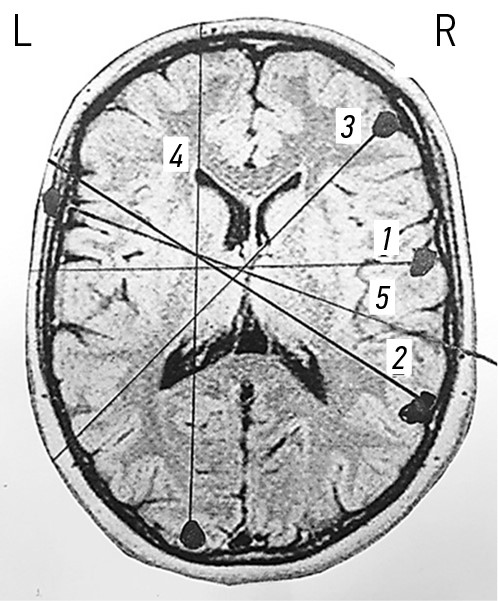

Ходы раневых каналов при огнестрельных проникающих осколочных ранениях черепа и ГМ, также примеры диагнозов продемонстрированы на рис. 3–7.

Рис. 3. Огнестрельные проникающие слепые простые и радиальные ранения черепа и головного мозга. Примеры диагнозов: 1 — минно-взрывное ранение (МВР). Огнестрельное осколочное слепое проникающее простое ранение правой лобной доли головного мозга; 2 — МВР. Огнестрельное осколочное слепое проникающее радиальное ранение правой лобной доли головного мозга; 3 — МВР. Огнестрельное осколочное слепое проникающее радиальное двуполушарное ранение левой теменной доли головного мозга.